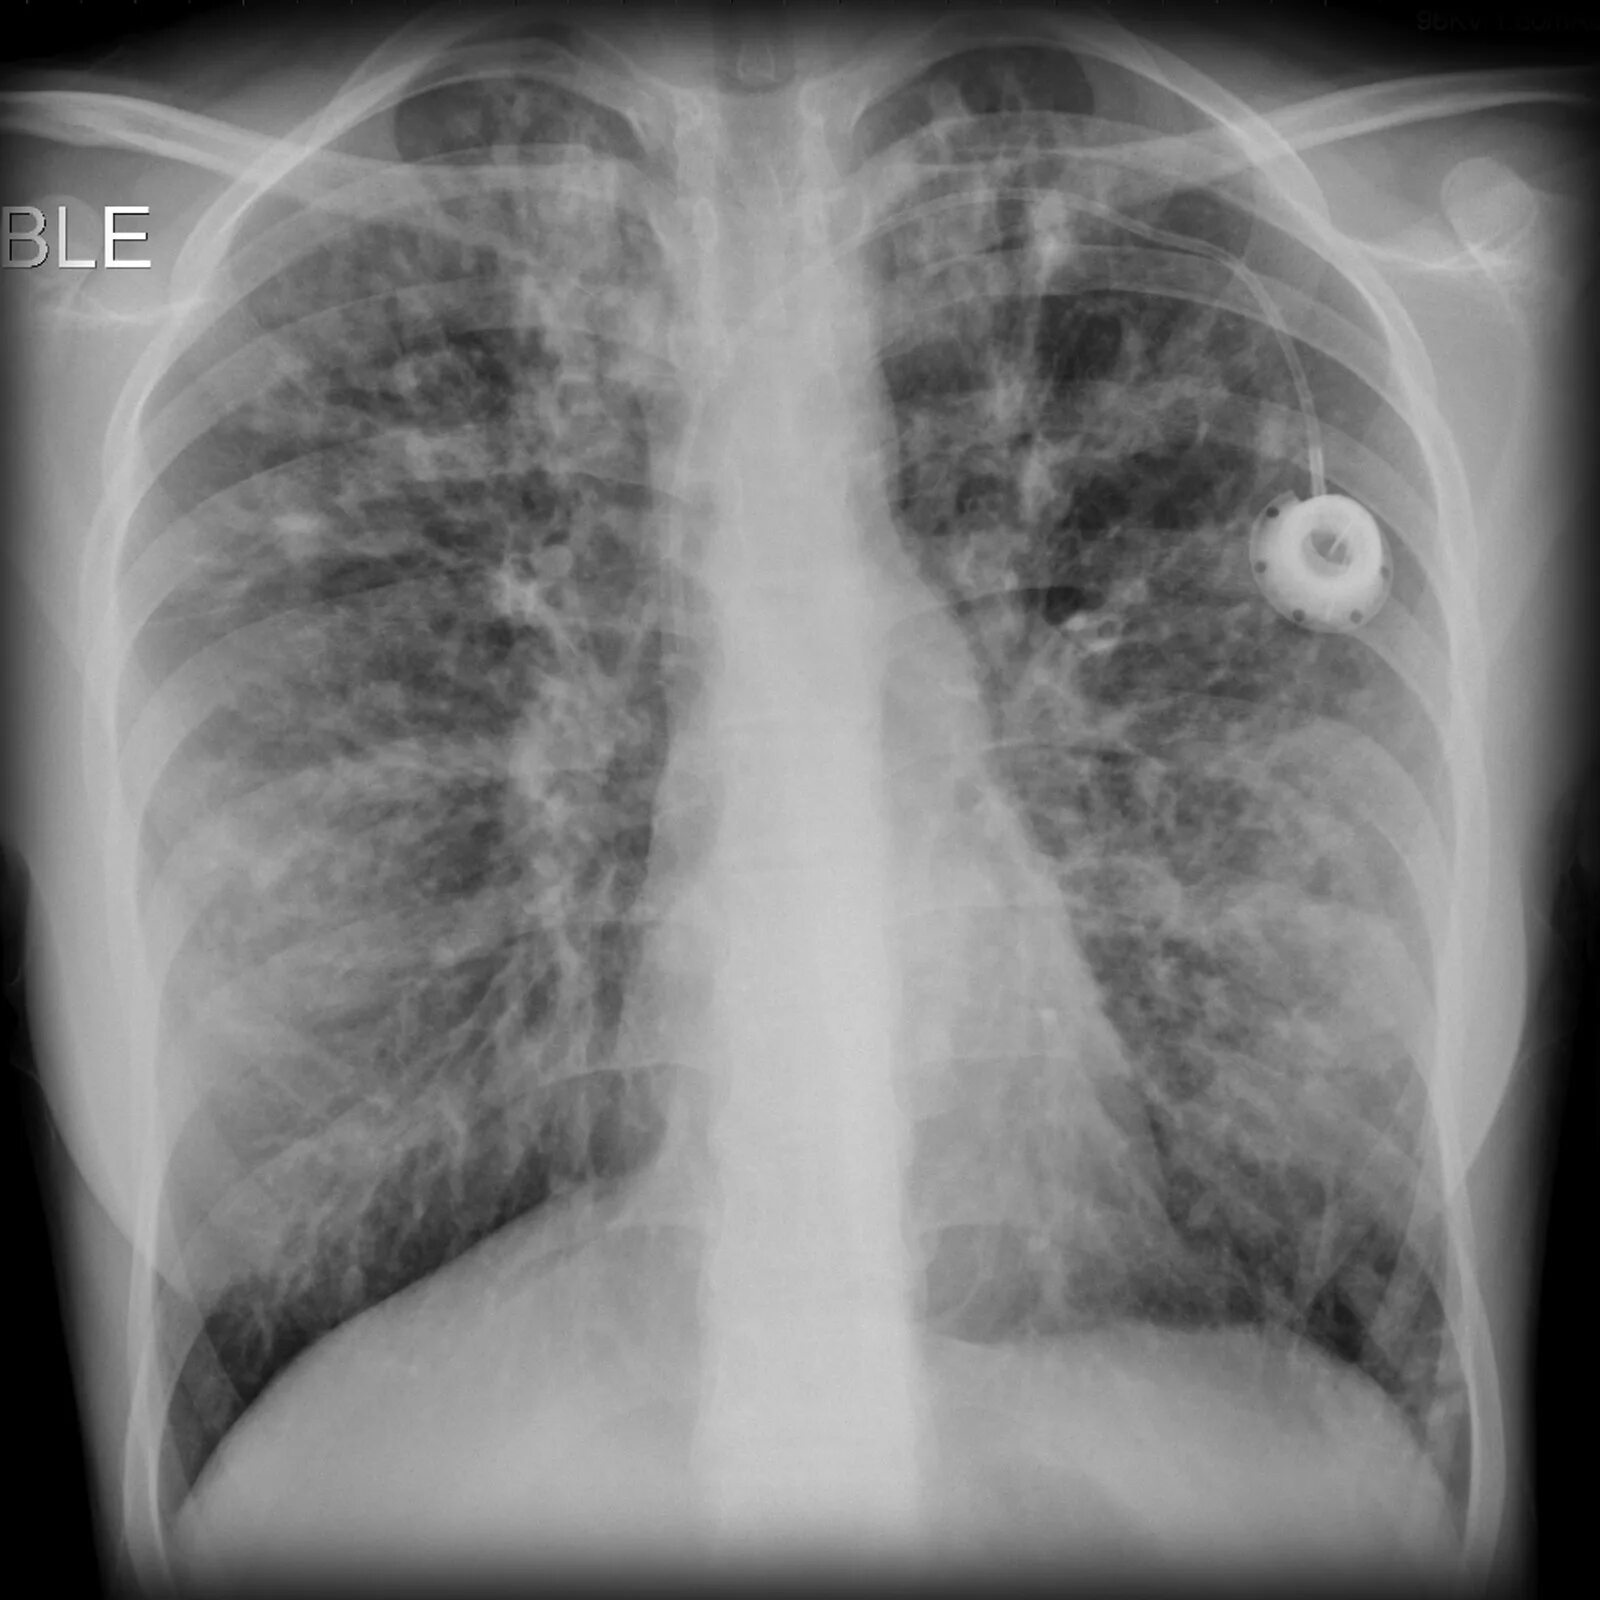

Как выглядит фиброз легких